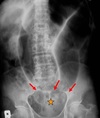

AXR: sentinel loop, pancreatic calcification